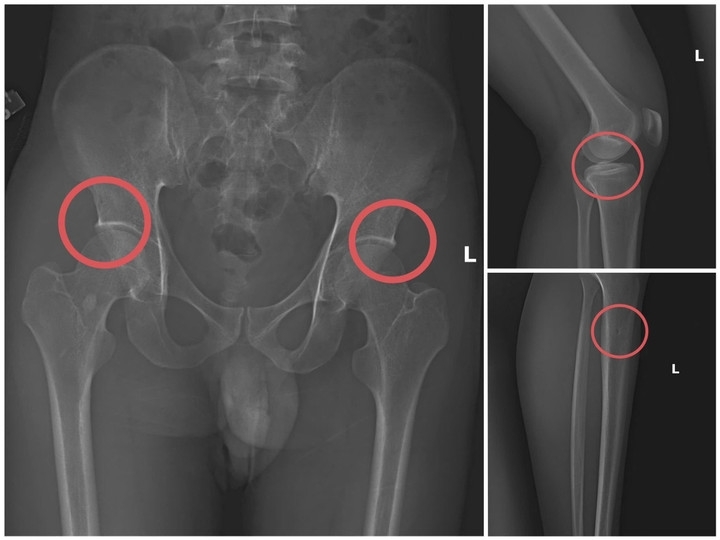

Công an tỉnh Phú Thọ vừa triệt phá đường dây tự gây thương tích có tổ chức, thủ đoạn tinh vi nhằm trục lợi hơn 6 tỷ đồng từ nhiều công ty bảo hiểm nhân thọ. Kẻ cầm đầu, chủ mưu là Tạ Minh Châu (SN 1995, cựu cán bộ Trung tâm Y tế huyện Cẩm Khê).

Dựa vào hiểu biết chuyên môn về y tế của cán bộ y tế, các đối tượng bàn bạc phân công thống nhất với nhau mua bảo hiểm của nhiều công ty bảo hiểm nhân thọ khác nhau. Sau đó, tự tạo ra thương tích để trục lợi bảo hiểm, gây thiệt hại số tiền lớn của các công ty bảo hiểm, đồng thời đây cũng là số tiền thu lợi bất chính của các đối tượng trong vụ án này.